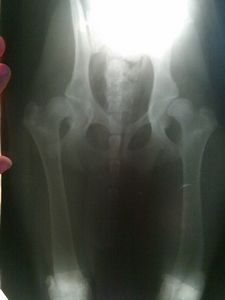

Расшифровка снимка заключается в изучении полного и сложного комплекса критериев, включающего положение тазовых костей, суставных поверхностей, головки бедренной кости; исследовании угла Horberg-Olson (параметра, отражающего тенденцию подвывиха бедра).

По итогам проведенного анализа различают 5 степеней положения бедра:

- I, или А: без признаков дисплазии;

- II, или В: средненормальное или промежуточное состояние;

- III, или С: легкая дисплазия;

- IV, или D. средняя дисплазия;

- V, или Е: серьезная, или тяжелая дисплазия.

Если суставы находятся в разном состоянии, заключение дается по итогам анализа худшего. Вышеперечисленные 5 стадий были установлены Комиссией по дисплазии бедра Международной Кинологической федерации (FCI). Таким макаром, оценка снимков, произведенных в разных странах — членах FCI, вполне сопоставима.